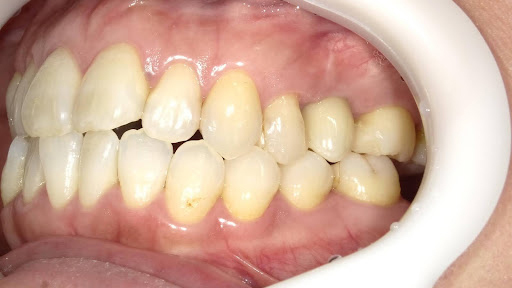

Before

枚方市のインプラントの症例

After

M・I 様 女性 70代

症状としては、左下56は、歯周病で欠損したと考えられるが、かなりの骨欠損をともなっていた。左上456に関しては、動揺が大きく、炎症が起き、排膿、および、歯性上顎洞炎を起こしていた。

治療法としては、動揺がひどくなってきて、炎症の症状もあったため、左上56の抜歯を希望。インプラント治療をその後、希望したため、左上4に関しては抜歯即時埋入。左上6に関しては、既存骨1から2mmでインプラント治療が厳しい状態であったが、グラフトレスサイナスリフトを行い、治療期間5か月はかかるということを説明して、インプラント埋入をおこないました。その後、2か月半後、大幅に骨が欠損している下顎56に対して、ショートインプラントを使用して、下顎神経の損傷を避けて、インプラント埋入を終えています。その後2か月後に光学印象で印象を行い、上顎刺億456歯、3ユニットのジルコニアブリッジを装着。下顎左側56に関しては、骨欠損が大きいため、歯冠長がだいぶ長くなるため、ジルコニアの連結冠を装着して治療を終えた。

治療結果は、上顎6に関しては、既存骨が少なく、厳しい治療ではありましたが、5か月で治療を終え、患者様の負担を最小限に抑えるができたと考えます。(従来のサイナスリフトでは、このようなケースでは1年以上、1年程度の治療期間がかかるか、治療が不可能と言われるケースだと考えます。)また、下顎は骨欠損が大きく、下歯槽管のリスクが起きることが考えられますが、ショートインプラントを使用することで安全に治療を行うことができました。

治療の期間・回数:治療期間5か月(上顎456 3ピースブリッジの治療は5か月(上顎既存骨が2mm程度しかなく、骨結合に時間がかかるケースであったために、5か月の治療期間が必要であった。)(左下56に関しては2か月半で治療を終えています。)治療回数は、13回。

治療の価格:1,474,000円(税込)

治療費の内訳:左上46および左下56のインプラント基本料(フィックスチャー及び手術費用、投薬費用、レントゲン費用、インプラント上部費用(アバットメントおよびジルコニアクラウンの費用用)330000円(税込み)×4本分 1320000円(税込)。左上5ジルコニアポンテック費用88000円(税込)。オプション費用、左上4抜歯即時埋入加算(人工骨費用を含む)+グラフトレスサイナスリフト費用 33000円(税込)、左上6グラフトレスサイナスリフト費用 33000円(税込)

治療のリスクや副作用:手術後に、痛みや腫れ、出血、合併症などを引き起こす可能性があります。噛む感覚がご自身の歯と異なる場合があります。見た目がご自身の歯と異なる場合があります。手術後にメインテナンスを継続しないと、インプラントが抜け落ちる可能性があります。